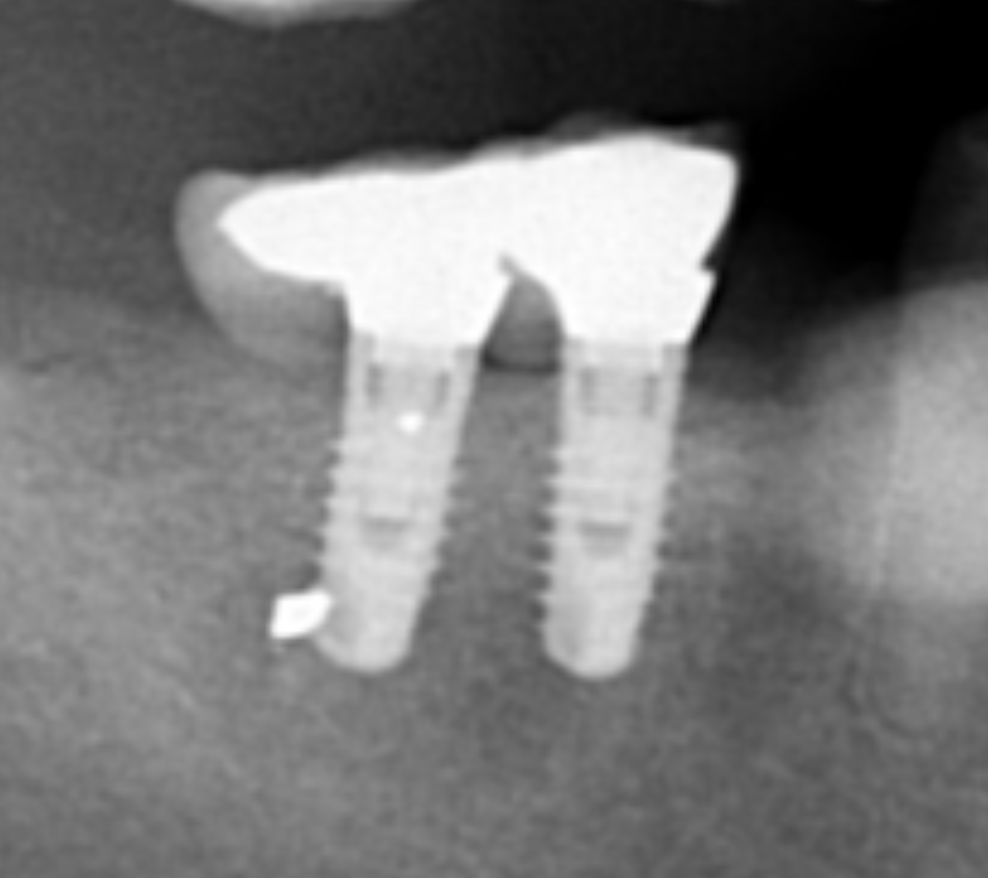

Hola comunidad, Os escribo porque me llegó un paciente con estos dos implantes en posición 46 y 47. No sabía muy bien de qué marca se trataba pero creí que [...]